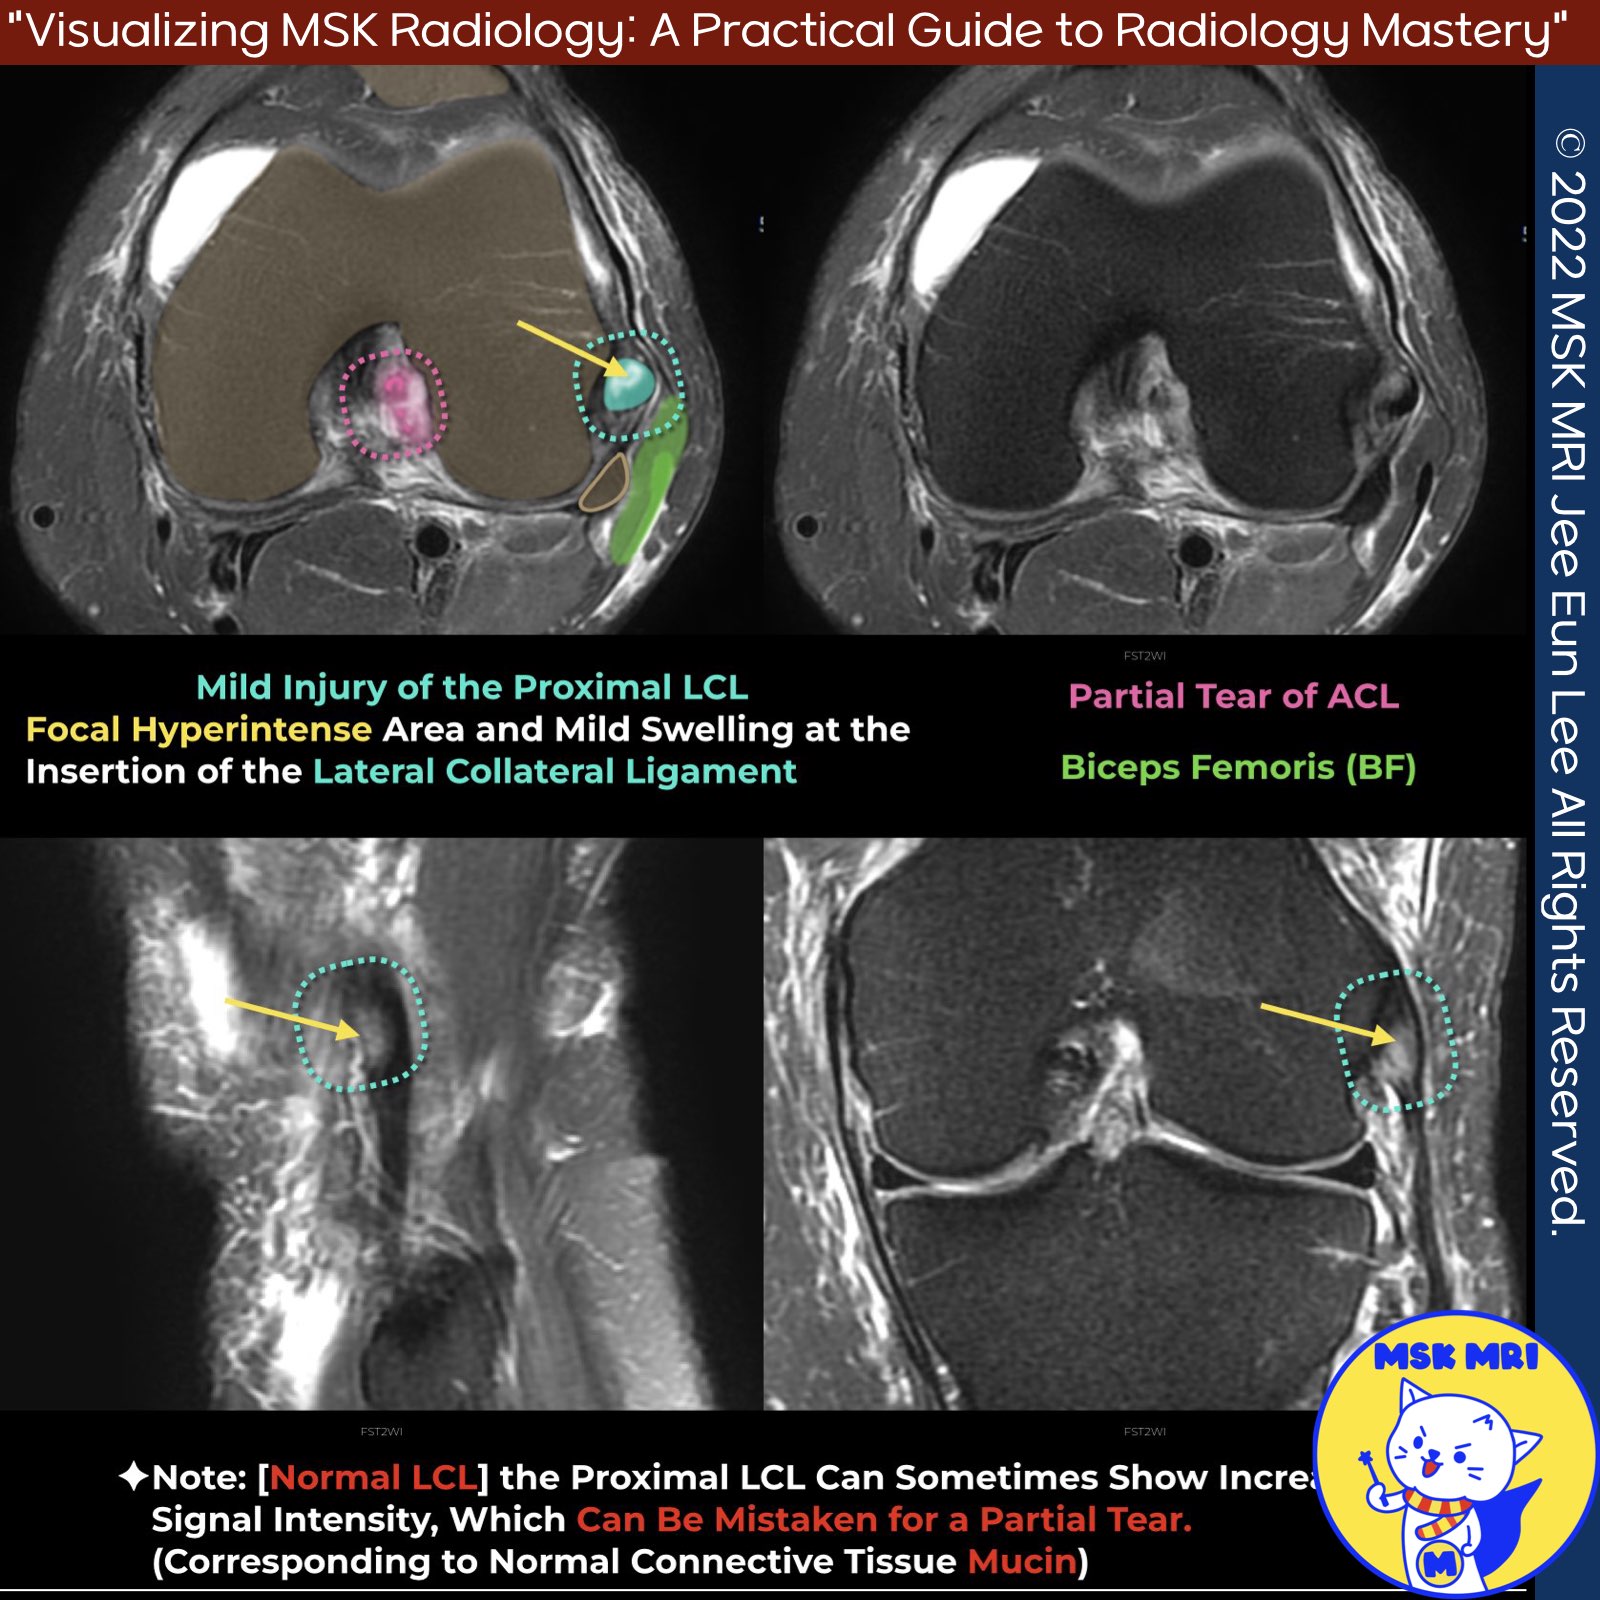

🧐 Case Presentation

- Focal hyperintense area and mild swelling at the insertion of the lateral collateral ligament

- Suggestive of mild injury of the proximal lateral collateral ligament (LCL)

✅ Point 1: Less Edema and Hemorrhage in LCL Injuries

- In LCL injuries, edema and hemorrhage are less frequent compared to medial injuries involving the medial collateral ligament (MCL)

- Even a grade 1 MCL injury, characterized by subcutaneous edema adjacent to an intact MCL, can demonstrate more surrounding soft tissue edema than an LCL injury

- In a grade 2 MCL injury, there is proximal MCL intraligamentous hyperintensity and thickening due to a partial tear of the superficial fibers

✅Point 2: Increased Signal in Proximal LCL

- The proximal LCL can sometimes show increased signal intensity

- This increased signal could be mistaken for a partial tear

- However, it may correspond to normal connective tissue mucin, especially in cases without a clear trauma history

- This possibility should be considered when interpreting such findings